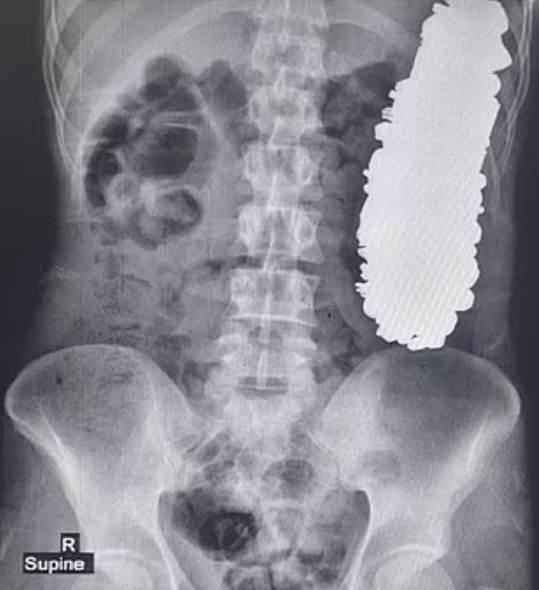

伊朗一名男子日前因為肚子劇痛而緊急送醫,醫師透過X光檢查後當場傻眼,發現他的胃部被重達3公斤異物塞得滿滿的,而這些異物真實身分曝光後,更是讓人大吃一驚。

根據《TVBS新聞網》、《鏡週刊》報導,這起離譜案例被刊載于《醫學案例報告雜誌》(Journal of Medical Case Reports)當中,這位37歲的患者因為長期胃部疼痛,加上頻繁嘔吐,使得他完全沒辦法正常吃東西或喝水,于是趕緊到醫院掛急診。

醫療團隊隨即為患者安排手術,過程中總共從他體內挖出452件金屬異物,包含螺絲釘、螺帽、各種鑰匙、徽章以及石頭等物品。醫師初步推測,這些東西應該都是患者在過去90天左右陸續吃下肚的,慶幸患者術後復原狀況相當不錯。

儘管患者吞下這麼大量的金屬異物,但經過詳細檢驗後卻發現,鏡沒有任何金屬製品進入消化系統其他部位。